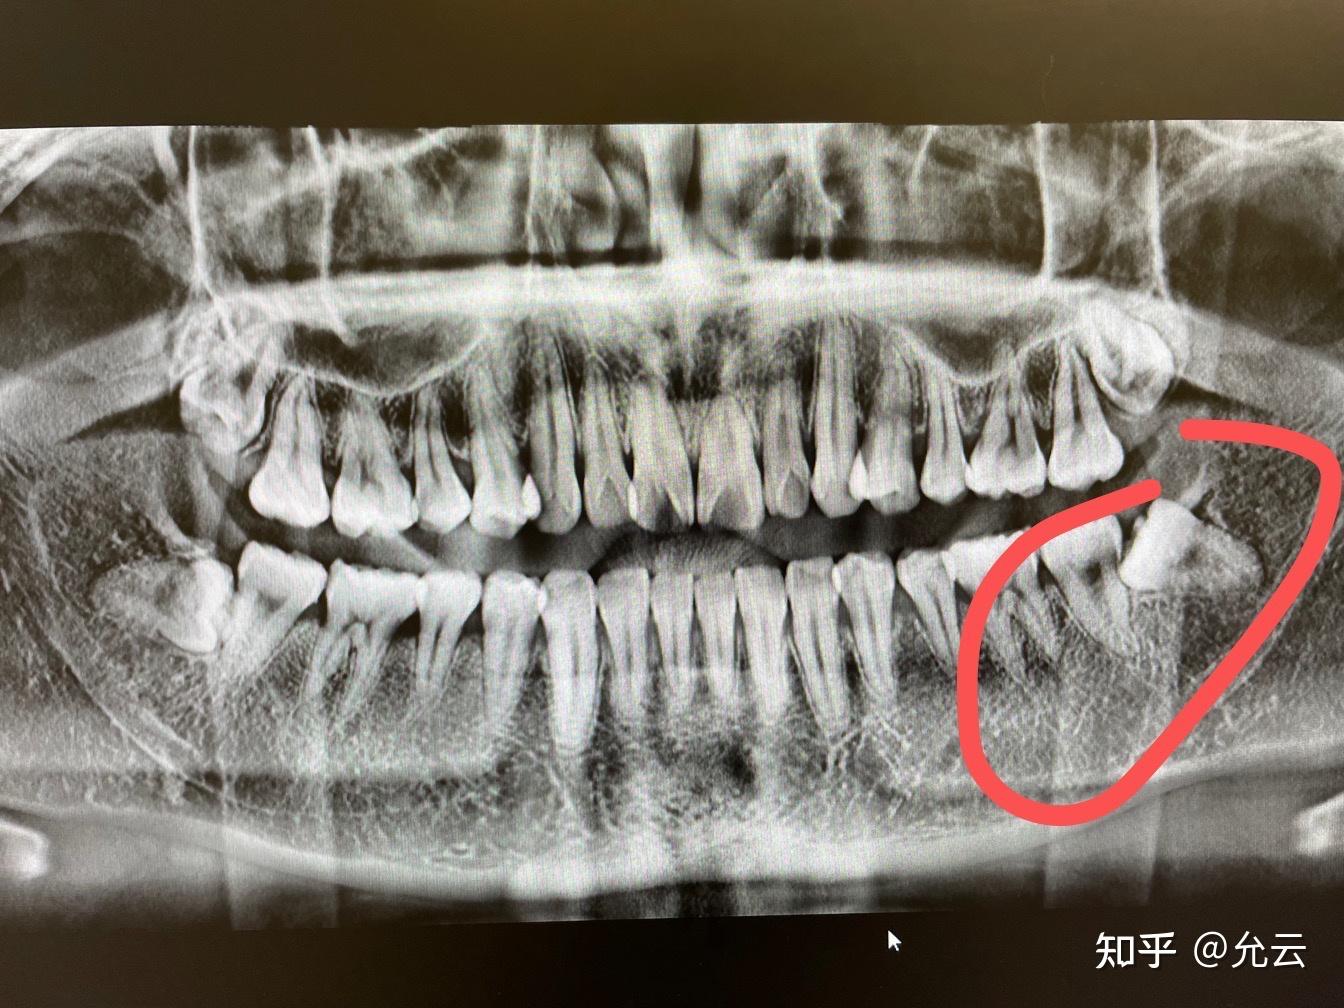

水平阻生智齿要拔除,顶着门牙要拔除

图片尺寸1280x720